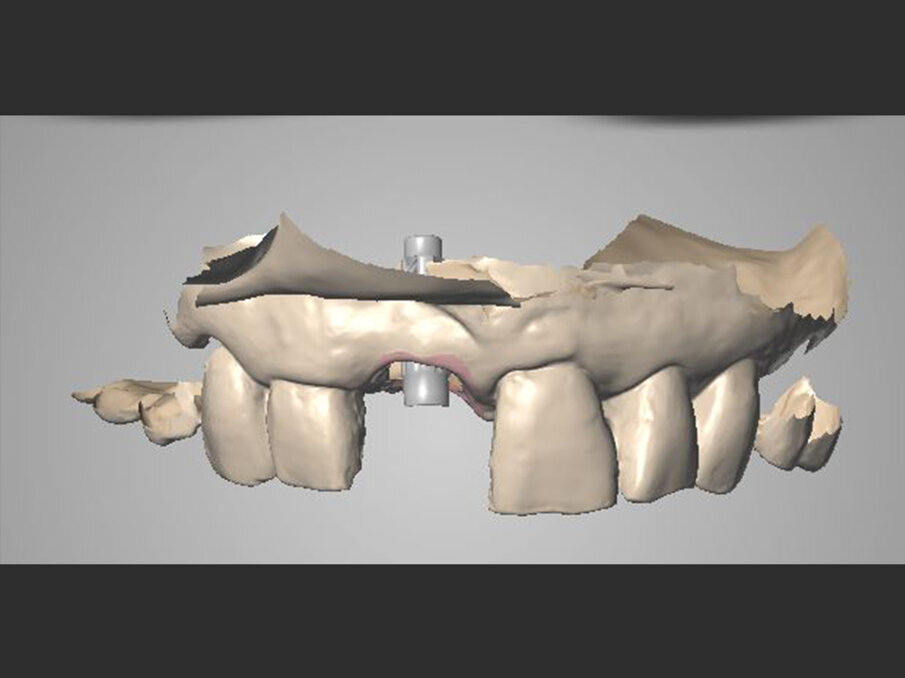

Un moncone in titanio per protesizzazione provvisoria (componente secondaria provvisoria - Straumann) viene modificato così da permettere un corretto alloggiamento della corona provvisoria e serrato manualmente. Protetto il canale della vite, il provvisorio viene forato in corrispondenza dell’accesso della vite protesica, posizionato in sede grazie alle alette e bloccato utilizzando del composito flow (G-aenial Universal flo - GC). Rimossa dal cavo orale, la corona provvisoria viene rifinita in laboratorio, completando il tragitto transmucoso in composito (Essentia Universal - GC) in modo tale da modellare un’area sotto-gengivale che sostenga i tessuti senza comprimerli. La riabilitazione provvisoria viene posizionata, avvitata e serrata a 20 N/cm. Il foro di accesso viene protetto con PTFE e sigillato con un’otturazione provvisoria (Telio CS onlay - Ivoclar), e i contatti occlusali vengono scaricati in modo tale da eliminare interferenze occlusali (Figg. 5, 6). Viene prescritta terapia farmacologica antibiotica, antidolorifica e sciacqui con collutorio a base di clorexidina digluconato. La paziente viene controllata a 7 giorni, 45 giorni e 90 giorni. A distanza di 3 mesi l’impianto viene considerato osteointegrato e i tessuti molli hanno raggiunto la loro stabilità. Il provvisorio viene quindi svitato (Fig. 7) e si procede tramite impronta ottica (Trios 3 - 3Shape) al trasferimento in laboratorio della posizione tridimensionale dell’impianto, della morfologia del tragitto transmucoso e della morfologia della componente sottogengivale della corona provvisoria (Figg. 8a, 9b). Una corona avvitata in zirconia con microstratificazione vestibolare viene confezionata come riabilitazione definitiva (Fig. 10). Superata la prova estetica, il manufatto viene consegnato e serrato a 35 N/cm. Il foro passante viene sigillato con PTFE e resina composita (G-aenial - GC) (Figg. 11, 12).

Figg. 8a, 8b - Acquisizione intraorale: visione frontale.

Figg. 9a, 9b - Acquisizione intraorale: tragitto transmucoso in visione occlusale.